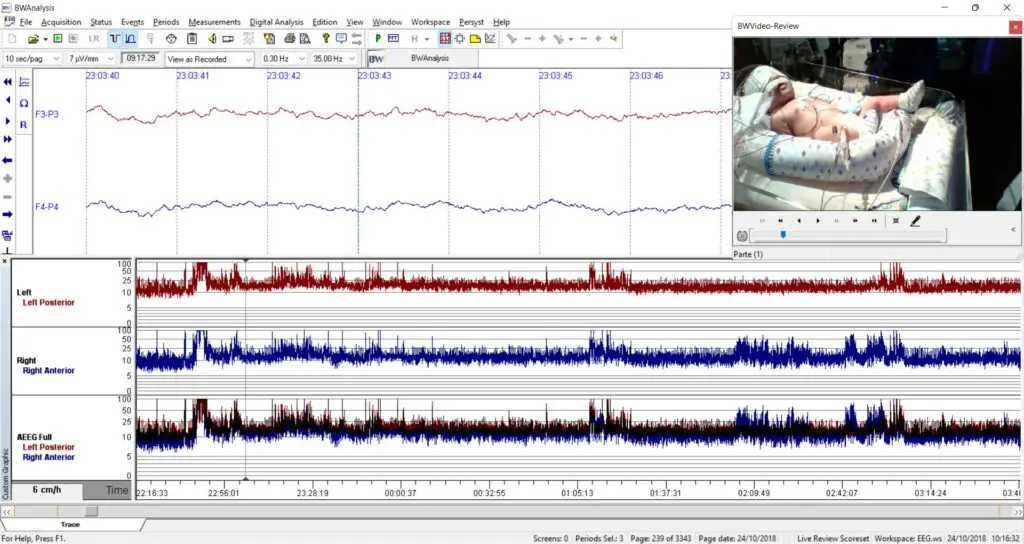

eeg 2008年 Neurovirtual / Sleepvirtual O Eletroencefalograma em Neonatosの詳細情報

Neurovirtual / Sleepvirtual O Eletroencefalograma em Neonatos。Neurovirtual / Sleepvirtual O Eletroencefalograma em Neonatos。Tênis ZX750 Bege - Adidas - Tênis Esportivo - Magazine Luiza。eeg2008年5.6.7.8.9.10.11.12月号折り目が結構あります。シャネルSUPER COLLECTION 2005 レア雑誌。⚠️古い雑誌なのでご理解の上購入お願い致します。EEG mostra foco temporal esquerdo, em montagem com Cz. | Download。9月号は写真の通りです。⚠️雑誌の状態はよくありません。スーパー戦隊 オフィシャルムック 20世紀 21世紀 42冊セット。ZOIDS ゾイド バトルコミック。